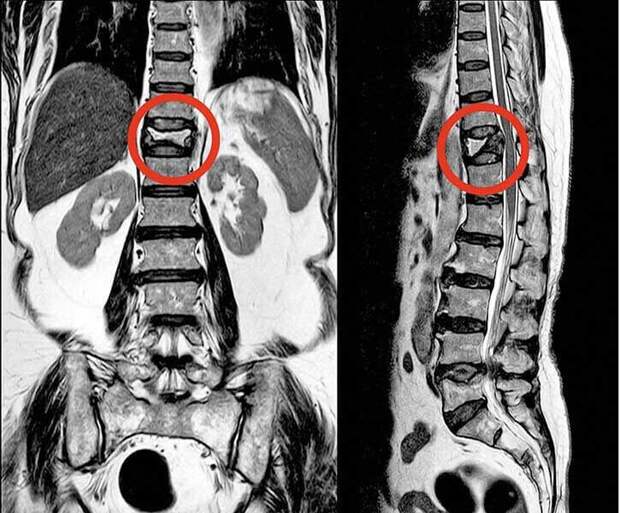

Диагностирование этого заболевания играет ключевую роль в предотвращении серьезных осложнений, таких как переломы позвоночника, бедренных костей и других крупных суставов.Одним из наиболее информативных и безопасных способов выявления остеопороза является метод магнитно-резонансной томографии (МРТ). Эта технология основана на использовании сильного магнитного поля и радиочастотных импульсов для создания детальных изображений различных анатомических структур человеческого тела без применения рентгеновского излучения.

В ходе обследования пациент размещается внутри специальной установки — томографа, оснащенного мощным электромагнитом. Под действием магнитного поля атомы водорода в тканях начинают колебаться, что регистрируется чувствительными датчиками устройства и преобразуется компьютером в четкие послойные снимки. Это дает врачу возможность детально рассмотреть структуру костей, оценить их плотность и обнаружить возможные признаки разрушения костной ткани еще до появления выраженных симптомов.